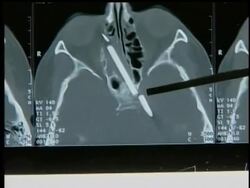

A woman in Germany has had a pencil removed from her head after more than 50 years.

HEADLINE: Woman has pencil removed from head (odd-germany-pencil-in-head) CAPTION: A woman in Germany has had a pencil removed from her head after more than 50 years. (Aug. 9) [Notes:ANCHOR VOICE] Imagine spending most of your life...